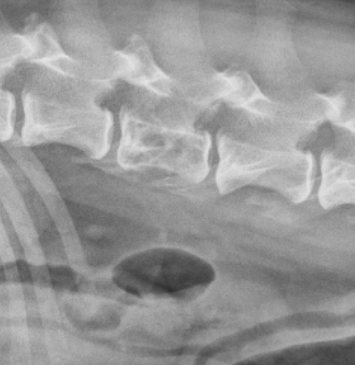

Q

what type of bone lysis is seen here?

A

moth eaten lysis, can see multiple small geographic areas of lysis